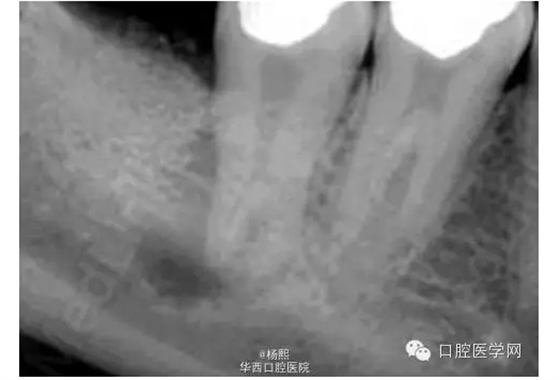

X線片示46、47牙合面牙體組織高密度影像,47牙輕度牙發(fā)育異常,髓室底較低,根尖周組織可見暗影。

討論:此病例屬于牙發(fā)育異常中的牛牙癥,為重度牛牙癥。牛牙癥(Taurodontism)是指牙髓頂至髓底的高度高于正常,而釉質(zhì)牙骨質(zhì)界的水平?jīng)]有改變、造成髓室向根尖延伸超過牙頸部,根分叉靠近根尖,牛牙癥 根據(jù)髓底向根尖方向位移的程度分為輕度、中度和重度。

?。?)X線片表現(xiàn):牛牙癥的異常特征的最直觀表現(xiàn)是在X線片上?;佳莱榉叫投皇窍蜓兰獠烤酆峡s窄的錐形。髓腔極大,髓室的根?向距離遠(yuǎn)大于正常。另外,牙髓腔在牙頸部沒有正常的縮窄,牙根極短。根分歧可能位于距牙根尖之上僅幾個毫米處。Shaw變異的程度,分類為輕度(hypotaurodont)、中度(mesotaurodont)和重度牛牙癥(hypertaurodont)。重度牛牙癥形態(tài)變異最大,牙齒根分歧位置接近牙根尖部,而輕度牛牙癥的變異最輕。